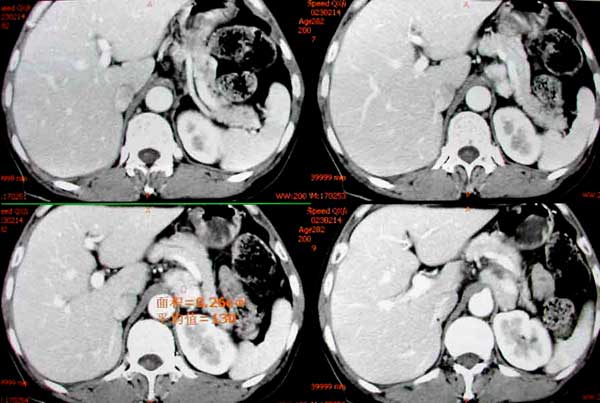

患者女,48岁,10年前右侧嗜铬细胞瘤及右肾切除术后,现血压持续增高。

liyj000发言:结合临床和ct表现:“腹膜后腹主动脉左侧见分叶状软组织块影,边界清,明显强化”可以诊断为嗜铬细胞瘤。

定性大家一致,现在具体定位到底是什么?是肾上腺内?好象不是,有一帧图象上肾上腺受推移,但轮廓存在。所以我说不是肾上腺内的。

不象是来源于左肾上腺。嗜铬细胞瘤约15%发生在肾上腺以外。

术后病理:左侧异位嗜铬细胞瘤